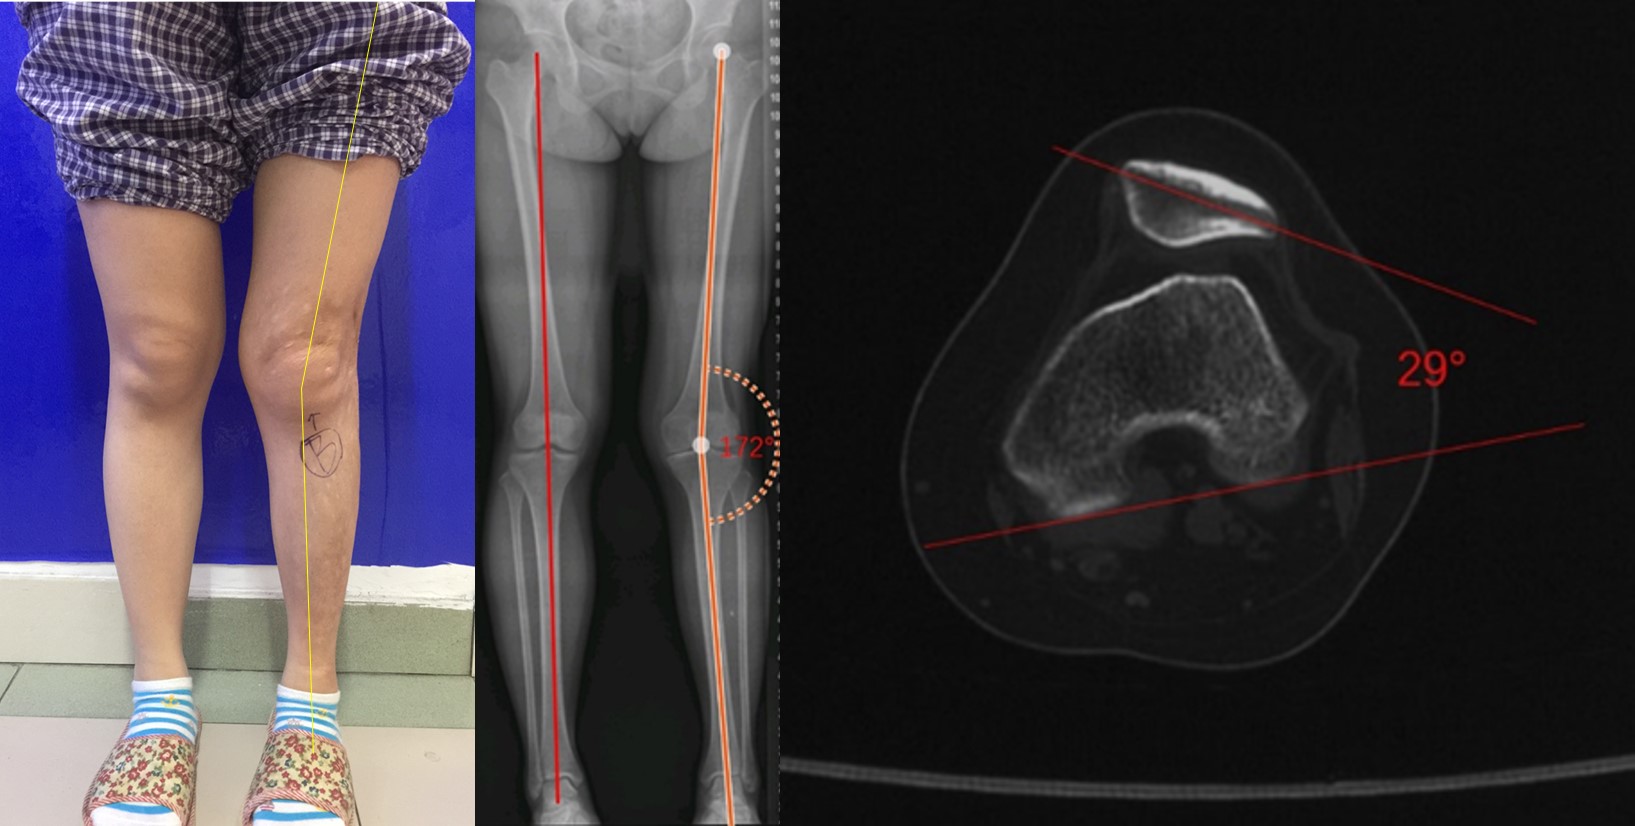

通俗地说就是腿型不好,谁都想有两条优美的大长腿,但现实是人群中有不少人在发育过程中形成了O型腿或X型腿等不好看的腿型。骨科医生叫做膝内翻畸形和膝外翻畸形,统称力线不良。而膝外翻畸形的患者容易并发髌骨脱位。

图7:膝外翻畸形患者,右下肢力线良好,左膝外翻畸形,髋膝踝角172°,髌骨半脱位,髌骨倾斜角29°

而相比膝外翻,还有一种畸形虽然也常见,但往往被忽视,就是拧毛巾畸形。也就是虽然腿型没有明显的内外翻,但却像被拧过的毛巾一样,当脚尖正对前方呈立正姿势站立时,髌骨却像斗鸡眼一样对视在一起;而只有两个脚尖呈外八字站立,髌骨才向正常一样正对前方,这是因为发育中股骨过度内旋或胫骨过度外旋导致的。有这种发育畸形的孩子往往还合并有髋臼发育不良,股骨过度前倾等髋部异常,股骨前倾角的正常范围是5-15°,大于20°为异常,大于25°易导致髌骨脱位。